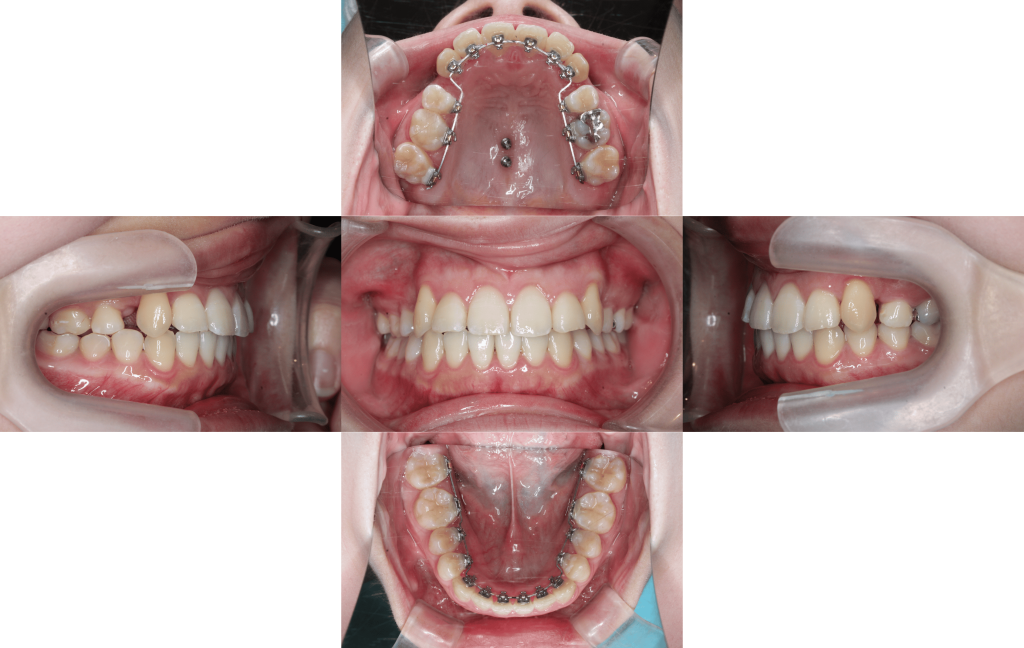

八重歯のでっぱりを治したい(治療期間6か月/治療回数8回)

Before

After

年齢層

20代

性別

女性

主訴

・八重歯のでっぱり・3⏇3凸凹・正中線のズレ

治療費用

¥1,287,000

治療期間

6か月(治療中)

抜歯

上顎両側第一小臼歯

矯正の装置

裏側矯正(舌側矯正)

副作用、リスク

歯肉退縮,歯根吸収,疼痛,咬合の違和感,装置の違和感,虫歯,歯肉炎